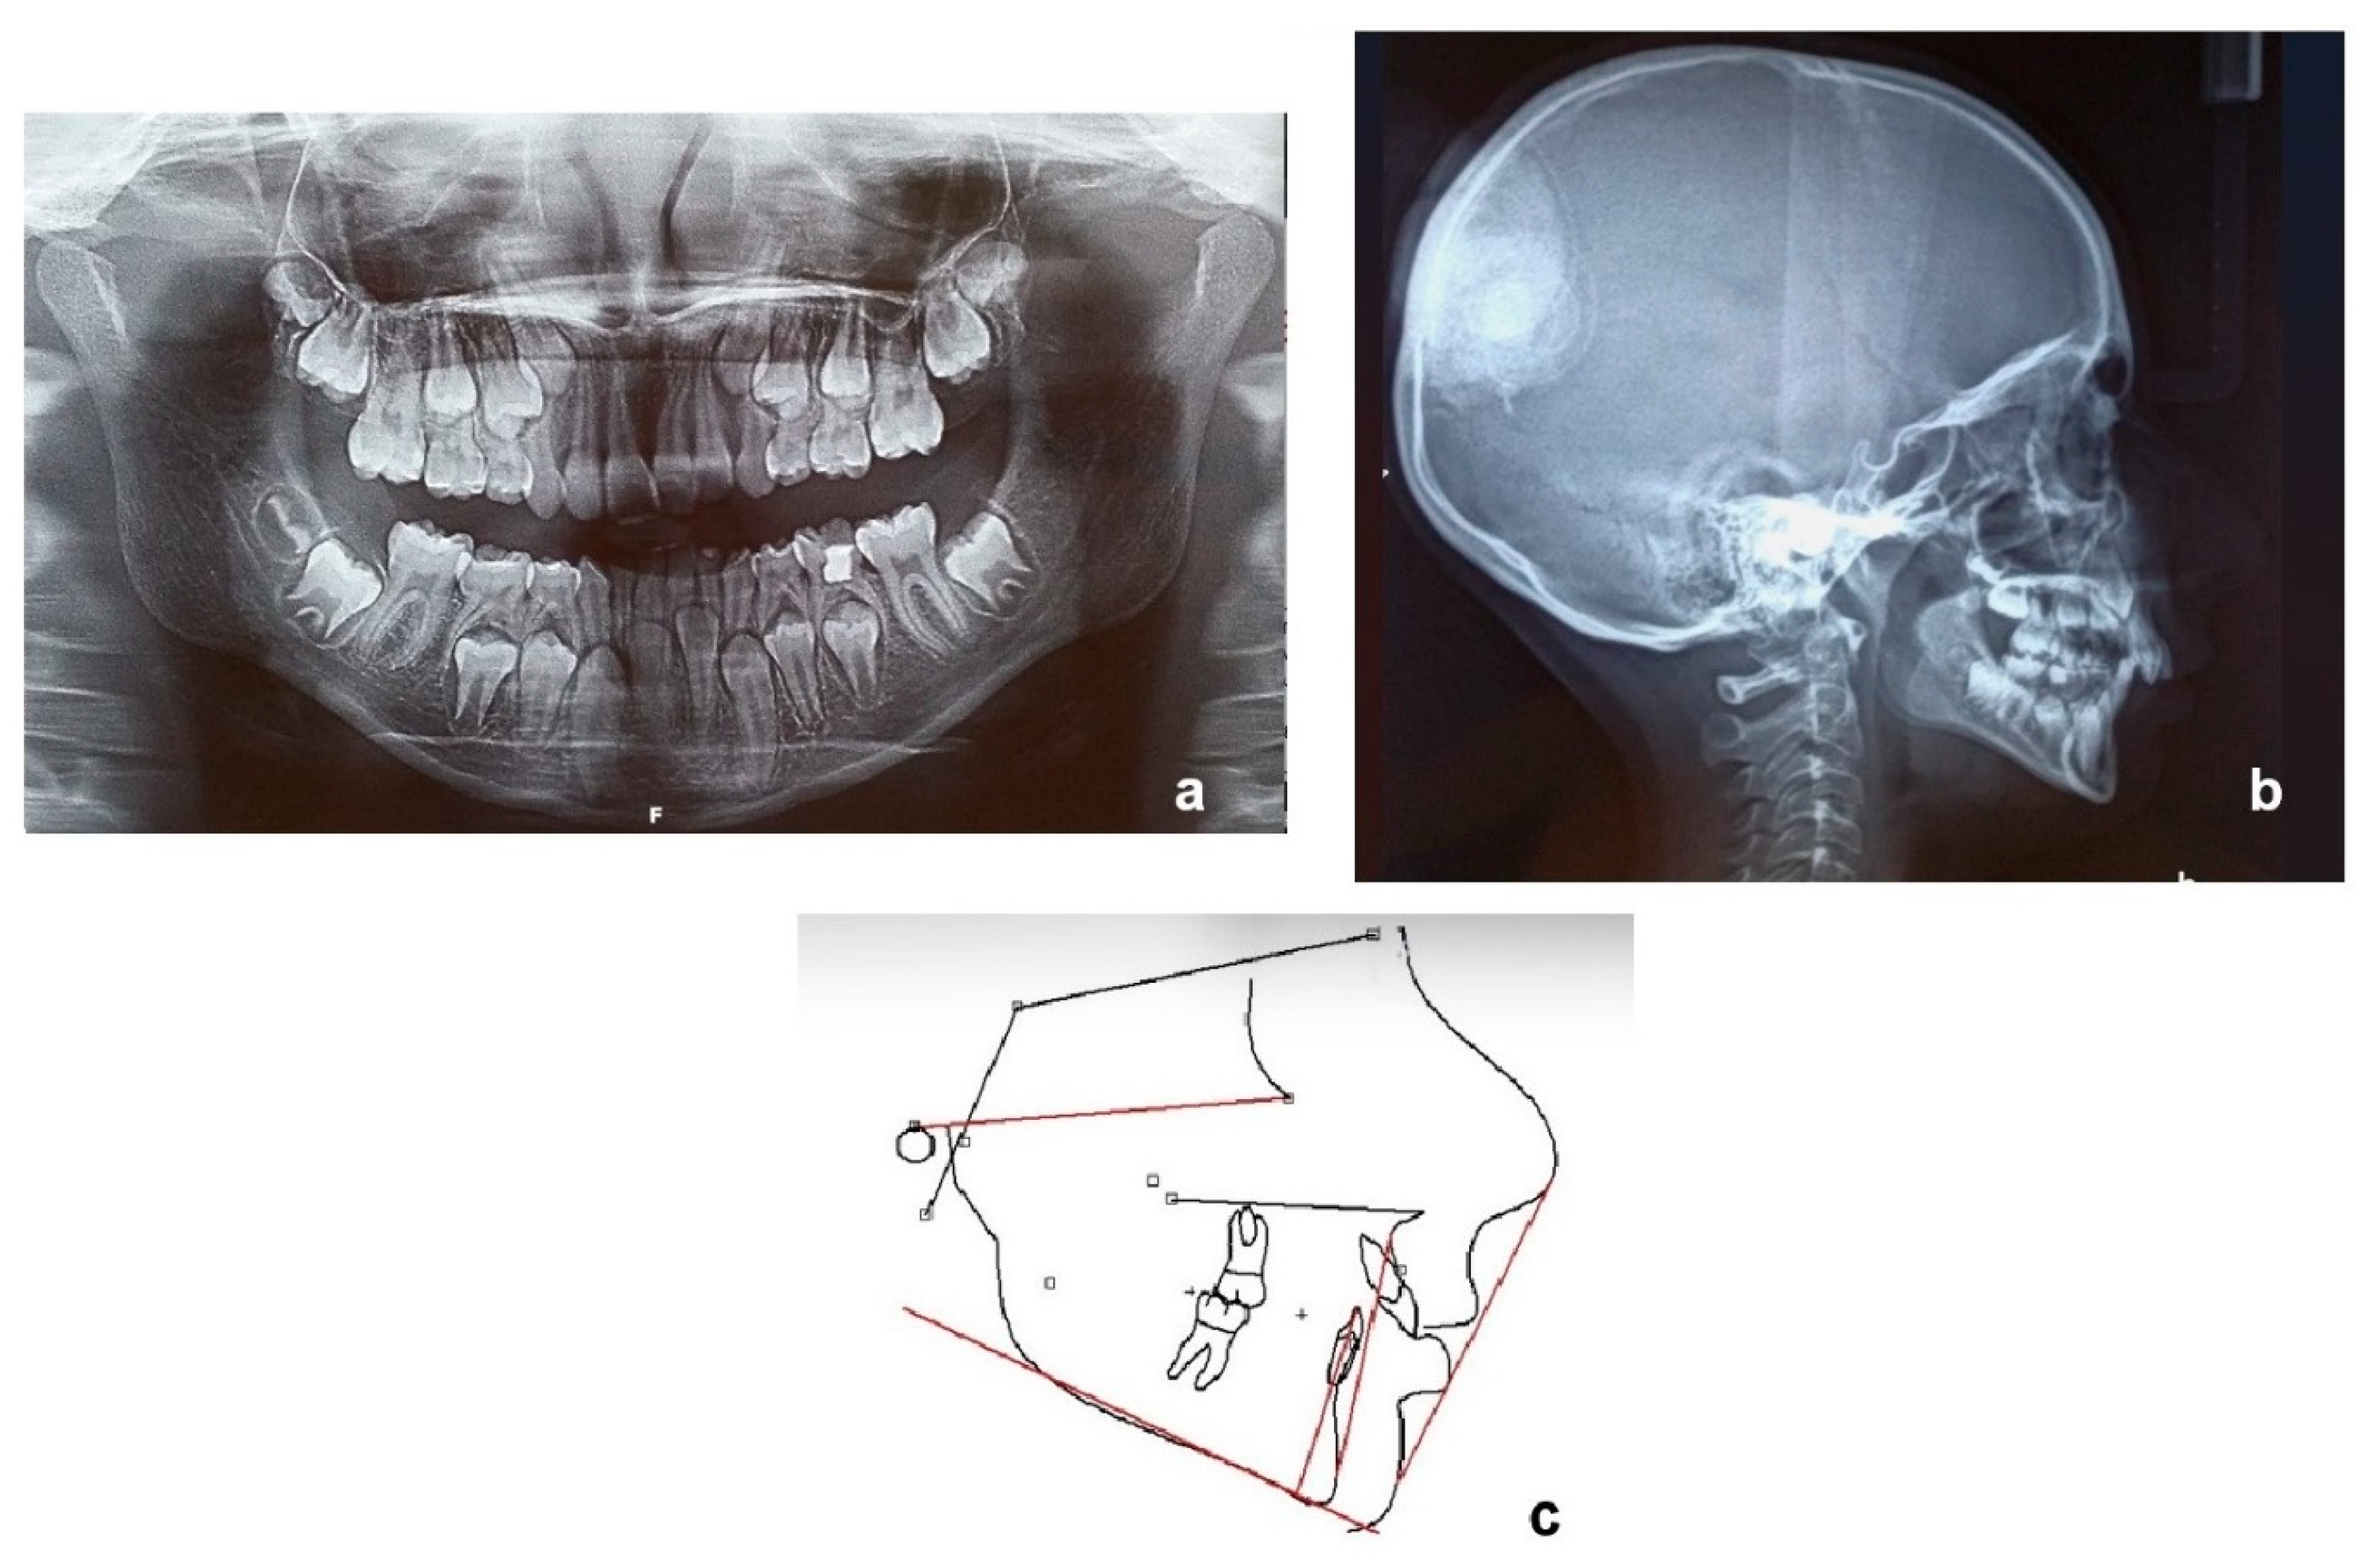

Final panoramic (Figure 9a) and lateral cephalometric X-ray (Figure 9b) and tracing (Figure 9c), as well as before and after treatment tracing superimposition (Figure 9d), are presented in Figure 9. Skeletal Class II relationship was reduced (ANB was calculated 5° at the end of therapy from 8° at the beginning (Table 2)), while Class I molar and canine relationships were achieved (Figure 10 and Figure 11). In Figure 12, a graphical abstract of the timeline of the steps that were followed in the treatment of this DTE case is presented.

Figure 9. Final panoramic (a), final lateral cephalometric X-ray (b), final tracing (c), before and after tracing superimposition (d).